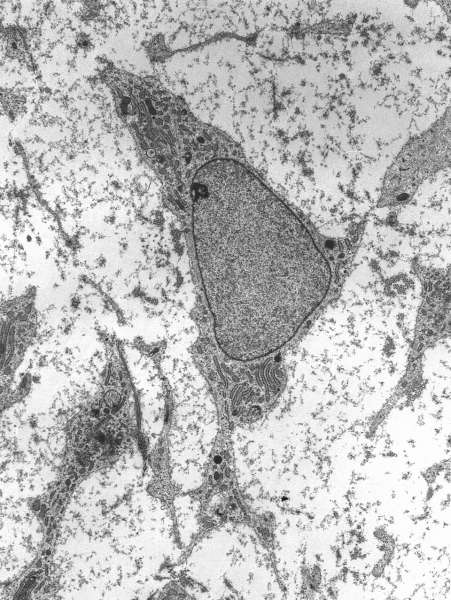

![[Img #77686]](https://noticiasdelaciencia.com/upload/images/01_2026/3769_960px-msc_high_magnification.jpg)

(Foto: Robert M. Hunt)